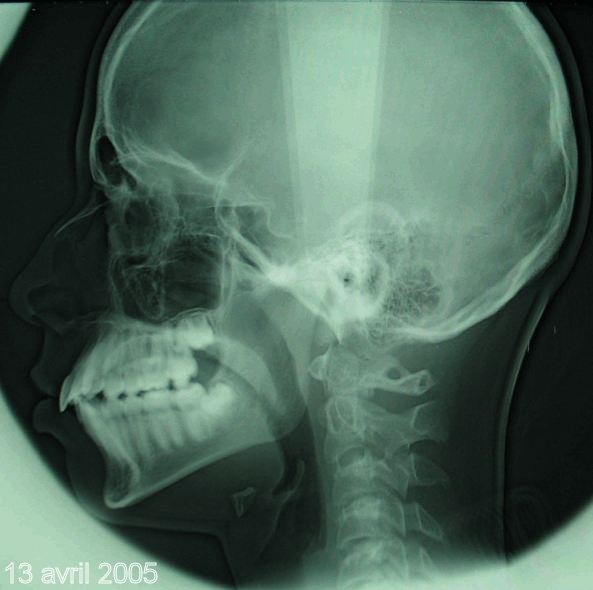

Bonjour, voici les clichés "panoramique" et "télé de profil" du 13 avril 2005 de Florent B. (voir les premiers posts pour comparer juillet 2001 et mars 2004 avec ce 13 avril 2005). J'espère que ces radios vous conviendront parfaitement pour les mesures? Aucun "trucage".

J'attends avec impatience et une grosse pointe de stress votre verdict clair, précis et concis sur l'évolution favorable ou défavorable du cas.

Je serai heureux si un ODF pouvait mesurer les valeurs 2001 et 2005 sur les téléRx et comparer celles-ci aux valeurs "normales" de vos tables de références.

Page précedente, bjc. Teleradiographie 2005.